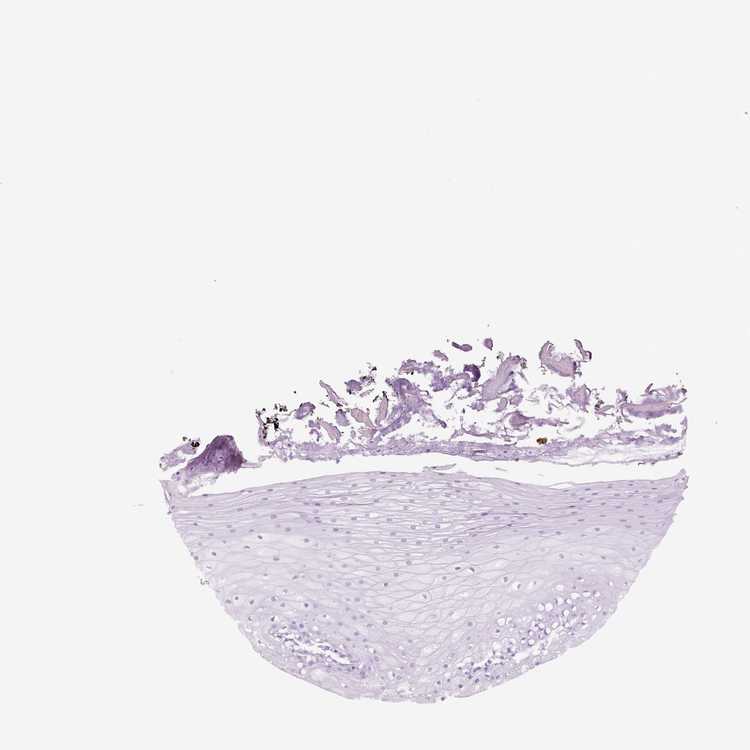

TISSUE PRIMARY DATA ORAL MUCOSA Show tissue menu

ORAL MUCOSA - Antibody stainingi

Antibody staining in the annotated cell types in the current human tissue is reported as not detected, low, medium, or high, based on conventional immunohistochemistry profiling in selected tissues. This score is based on the combination of the staining intensity and fraction of stained cells.

Each image is clickable and will lead to virtual microscopy that enables deeper exploration of all samples and also displays staining intensity scores, fraction scores and subcellular localization as well as patient and tissue information for each sample.

Squamous epithelial cells Not detectedNot detectedNot detectedNot detectedNot detectedNot detectedNot detected